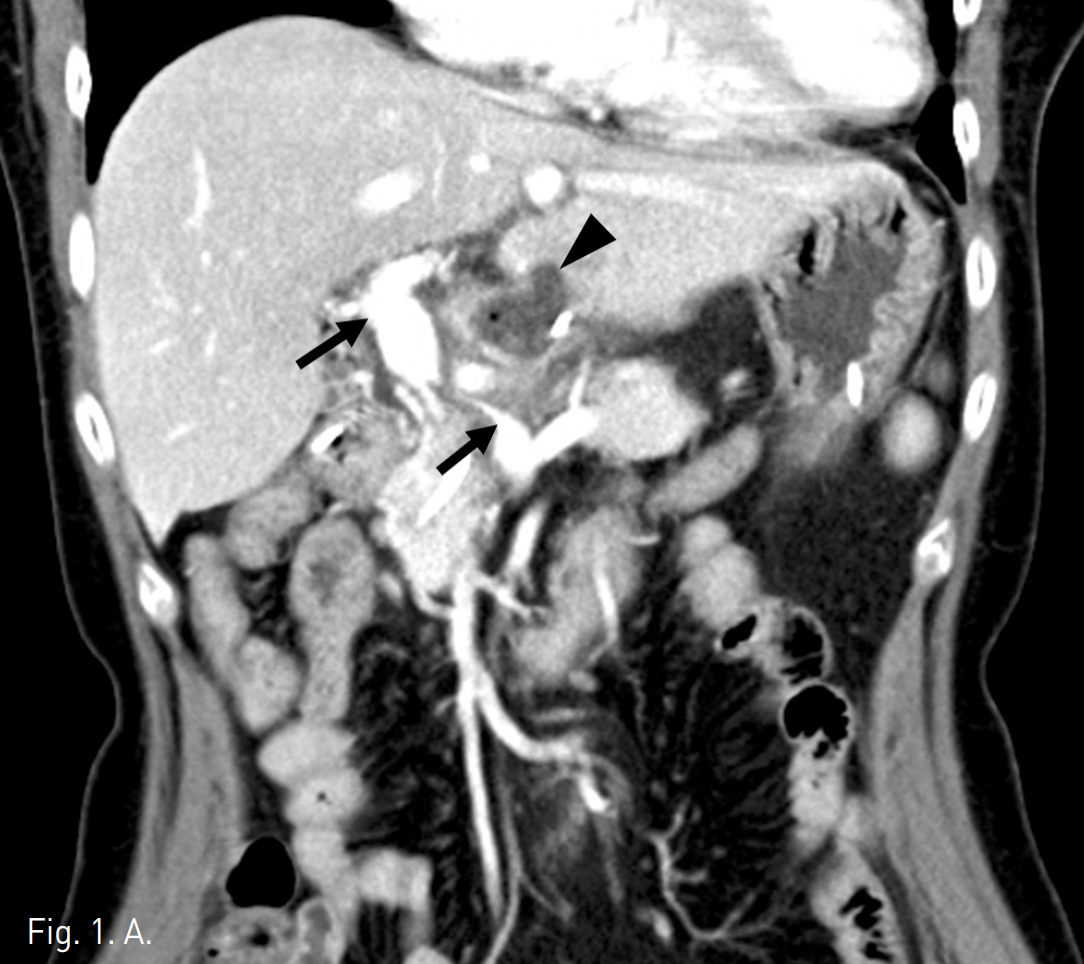

21G Chiba needle을 이용하여 경피적으로우간문맥(P6)을 천자한 후 0.035"guidewire (Guide wire M, Terumo, Tokyo, Japan)를 이용하여 5F catheter (Soft Vu, AngioDynamics, Queensbury, NY)를 주간문맥에 위치시킨 후 문맥조영술을 시행하였음. 주문맥에 4~5cm의 심한 협착(90%)이 있으며 주문맥 주변으로 해면상 변환 (cavernous transformation)에 의한 곁순환 혈관(collateral vessel)이 보임. 협착 원위부의 문맥압은 26mmHg, 위창자간막정맥(supsuperior mesenteric vein, SMV)과 비장정맥(splenic vein)의 압력은 17mmHg로 협착 근위부와 원위부의압력차는 9mmHg임(Fig 2A).

Fig. 2

A. P6 is punctured by a 21G needle percutaneously and catheter is introduced into main portal vein. On portogram, thereis a short segmen talpor tal stenosis of 4~5cm in length and many small collateral vessels around main portal vein as cavernous transformation. Pressure gradient is 9 mmHg. (portal vein; 26mmHg, SMV and splenic vein; 17mmHg).